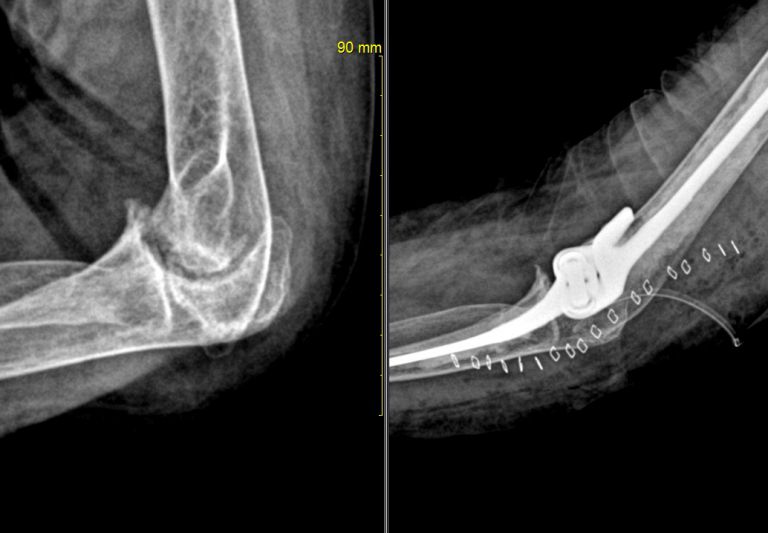

무릎 인공관절

무릎 인공 관절